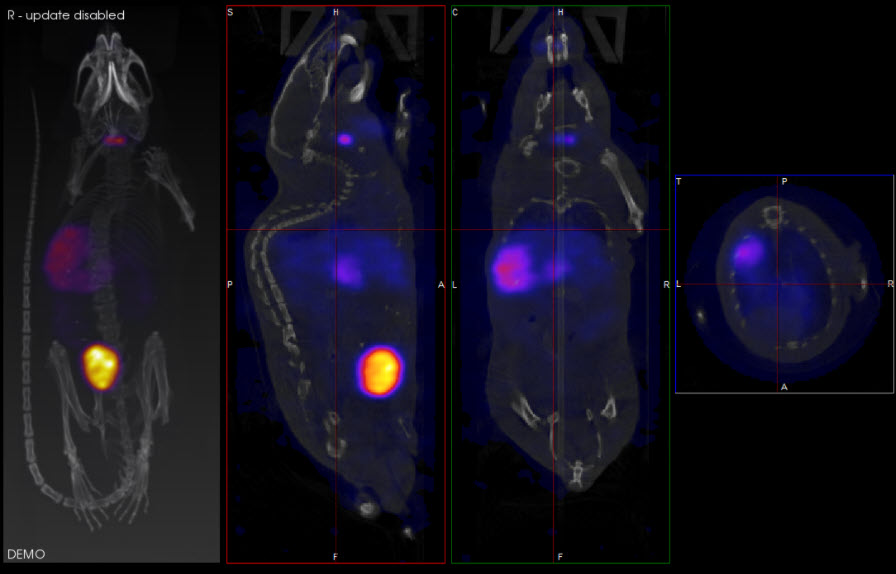

In the example image below, the transversal view is the active view. The ← and → keys move the crosshairs towards the L (left side) and R (right side) in the transversal slice, respectively. Moving through the object to the left or right steps through the sagittal plane of the object; thus, the sagittal slice changes.

The ↑ and ↓ keys will move the crosshair towards P (posterior side) and A (anterior side). Both these sides are also visible in the sagittal slice of the object (rotated 90-degrees). Using the ↑,↓ keys in the transversal plane will shift the vertical crosshair in the sagittal plane, and step through the coronal views of the object.